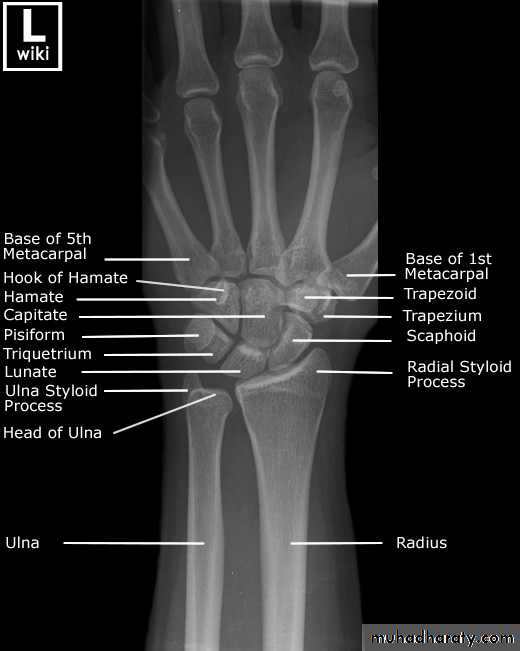

• عمليا يتم تصوير الرسغ والمرفق والكتف لمن يبدوا ظاهرا دون سن العشرين عاما من العمر. ويصور الحرقف لمن بدا في اواسط العقد الثالث من العمر او اقل, والنهاية الانسية للترقوة والتحام القص بالرهابة لمن تجاوز ذلك.

55• معدل ظهور والتحام المراكز التعظمية تبعا للعمر:

• 2) في السنة الاولى( نهاية الشهر الثالث) يظهر (متع) للعظم الرؤيسي والشصي

• وفي الشهر السابع يظهر متع للنهاية السفلى للكعبرة, وفي الشهر العاشر يظهر

• متع للعظم المثلث من عظام الرسغ.

• 2) السنة الثانية يظهر المركز التعظمي للعظم الهلالي الرسغي.

• 3) في نهاية السنة الرابعة يظهر متع لرأس الكعبرة.

• 4) وفي بداية السنة الخامسة يظهر متع للعظم المربع المنحرف وفي نهاية السنة االخامسة يظهر المركز التعظمي لعظمي شبه المنحرف والزورقي الرسغيين.

• 5) في سن السادسة يظهر متع للقمة الانسية لعظم العضد والنهاية السفلية لعظم الزند.

معدل التحام مراكز التعظم:

574) في سن 17-18 تلتحم النهايتان السفليتان للكعبر والزند كل مع عمده.